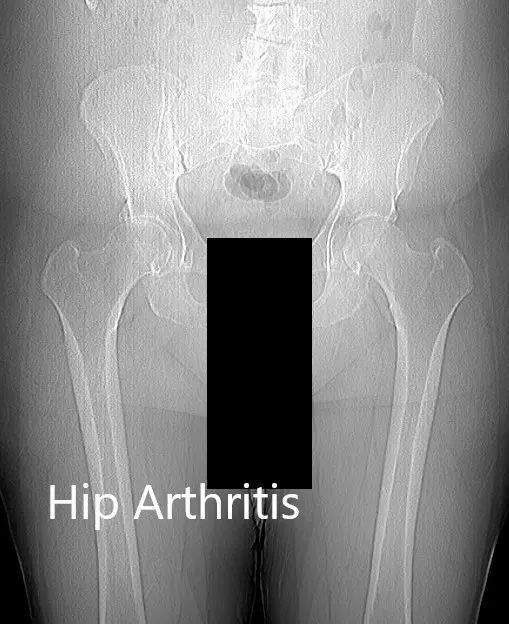

There was no fixed deformity in the coronal, sagittal and axial plane. The bilateral lower extremity pulses were 2+ and comparable. There was no distal neurological deficit. Imaging revealed severe osteoarthritis of both hips with subchondral cysts, sclerosis, and osteophyte.

Preoperative X-ray of the patient’s pelvis with both hips

Preoperative X-ray of the patient’s pelvis with both hips.